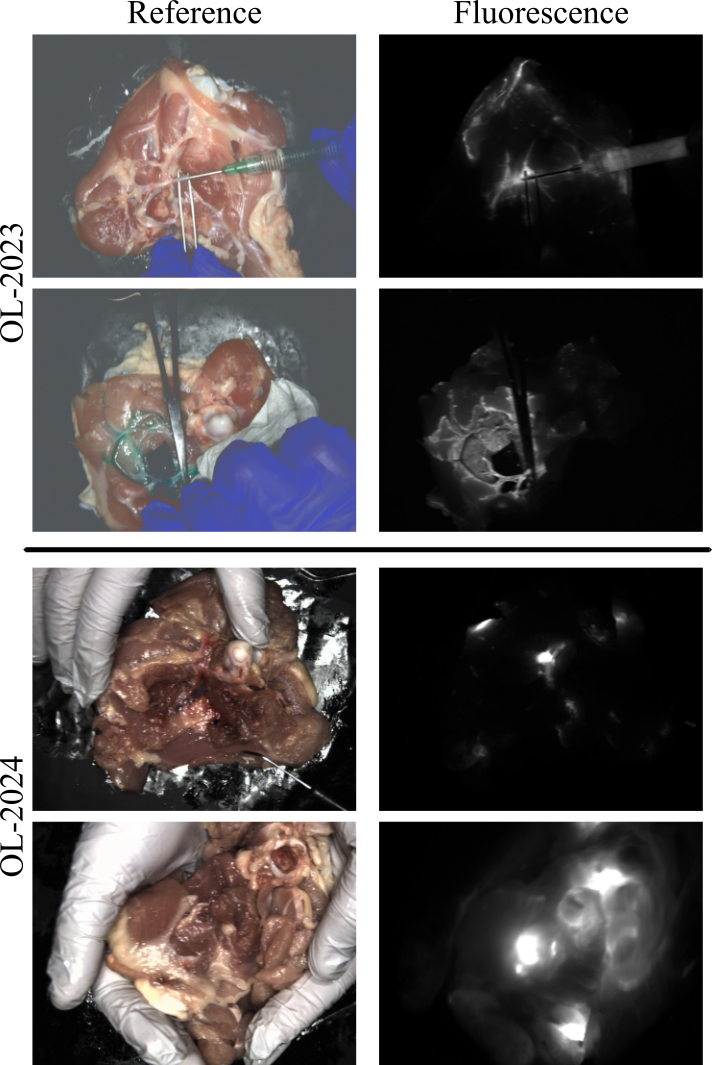

Figure 2: Dataset Example Images: Here we show two example images for both OL-2023 and OL-2024. OL-2023 focuses on vasculature where as OL-2024 focuses on local fluorescent regions.

To the best of our knowledge, the OL-2023 dataset [8] is currently the only publicly available FGS dataset with both FV and RV. OL-2023 contains 100 minutes of mock surgery video using the blue blood chicken surgical model [11]. OL-2023 contains a number of surgical actions with a large focus on perfusion imaging with fluorescent injection sites being primarily vascular structures and focusing on slower motion scenarios. We expand the scope of this data with the new OL-2024 dataset with challenging motion scenarios and a focus on cancer and lymphatic surgeries. We follow a similar experimental setup that was used to create OL-2023; we use the OnLume Avata clinical FGS imaging system (OnLume Surgical, Madison, WI), chicken thighs as our mock surgical patient, and high concentrations of indocyanine green (ICG) to generate very bright fluorescence that can be used as ground truth FV without LLL. In addition to the new mock surgical data we also capture a calibration and real noise test set. All videos are at 15 frames per second with a resolution of 768 by 1024 for both the RV and the FV. Dataset available at [12].

OL-2024 and OL-Combined: The OL-2024 dataset contains 130 minutes of new mock surgical video, each video contains aligned RV, Rtvsubscriptsuperscript𝑅𝑣𝑡R^{v}_{t}italic_R start_POSTSUPERSCRIPT italic_v end_POSTSUPERSCRIPT start_POSTSUBSCRIPT italic_t end_POSTSUBSCRIPT and low-noise FV, Stsubscript𝑆𝑡S_{t}italic_S start_POSTSUBSCRIPT italic_t end_POSTSUBSCRIPT frames. OL-2024 has a focus on simulating surgeries similar to cancer resections or lymphatics while also introducing more challenging motion scenarios. We primarily inject ICG into muscle or fat causing irregular fluorescent blooming with substantial scattering, modeling surgeries with patches of embedded fluorescent tissue. Example images from OL-2023 and OL-2024 are shown in Fig. 2. Additionally, unlike OL-2023, videos in OL-2024 are largely contiguous, up 18 minutes, allowing testing of long range dependencies. While these long videos are not the focus of this work we expect them to be important in future work. We combine OL-2023 and OL-2024 into core dataset, OL-Combined which we split into a training and testing set.